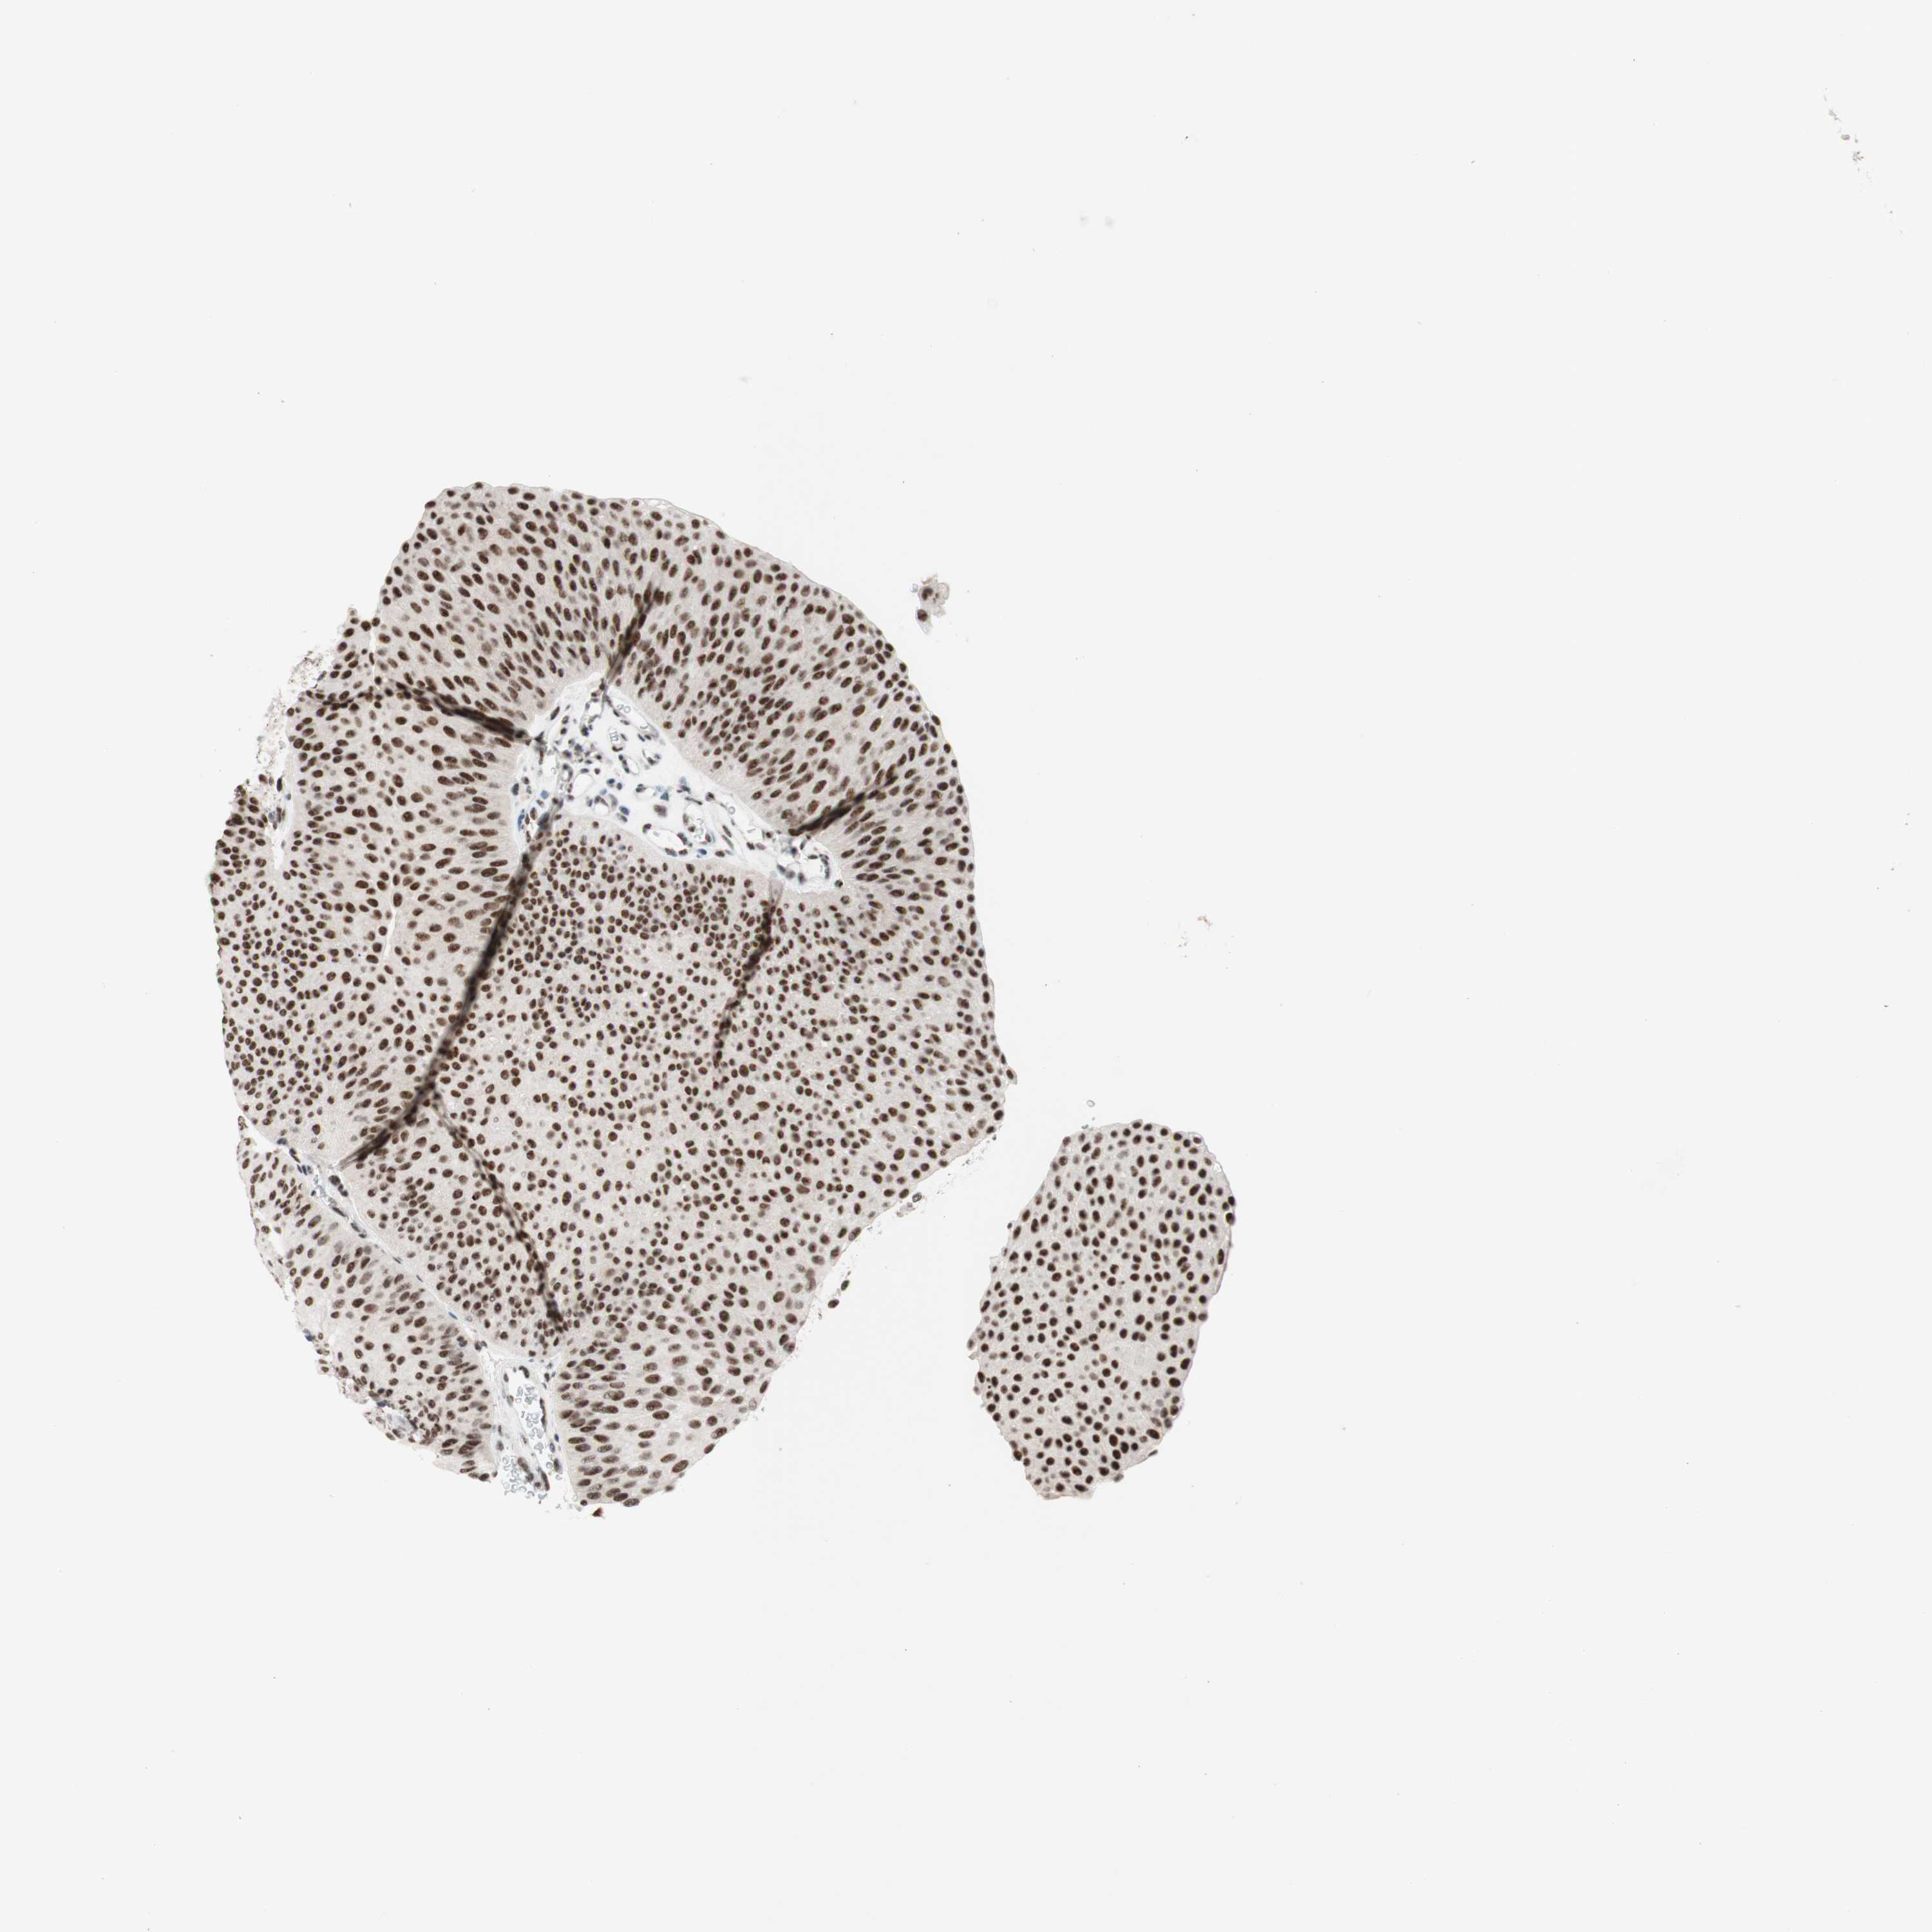

UROTHELIAL CANCER - Protein expressioni

A mouse-over function shows sample information and annotation data. Click on an image to view it in a full screen mode. Samples can be filtered based on level of antibody staining by selecting one or several of the following categories: high, medium, low and not detected. The assay and annotation is described here.

Note that samples used for immunohistochemistry by the Human Protein Atlas do not correspond to samples in the TCGA dataset.

Antibody stainingi

Antibody staining in the annotated cell types in the current human tissue is reported as not detected, low, medium, or high, based on conventional immunohistochemistry profiling in selected tissues. This score is based on the combination of the staining intensity and fraction of stained cells.

Each image is clickable and will lead to virtual microscopy that enables deeper exploration of all samples and also displays staining intensity scores, fraction scores and subcellular localization as well as patient and tissue information for each sample.

Antibody HPA038051

Antibody HPA059070

Antibody CAB012448

Staining

High

Medium

Low

Not detected

Intensity

Strong

Moderate

Weak

Negative

Quantity

>75%

75%-25%

<25%

None

Location

Nuclear

Cytoplasmic/membranous

Cytoplasmic/membranous,nuclear

Urothelial carcinoma, High grade

Urothelial carcinoma, Low grade

Urothelial carcinoma, NOS